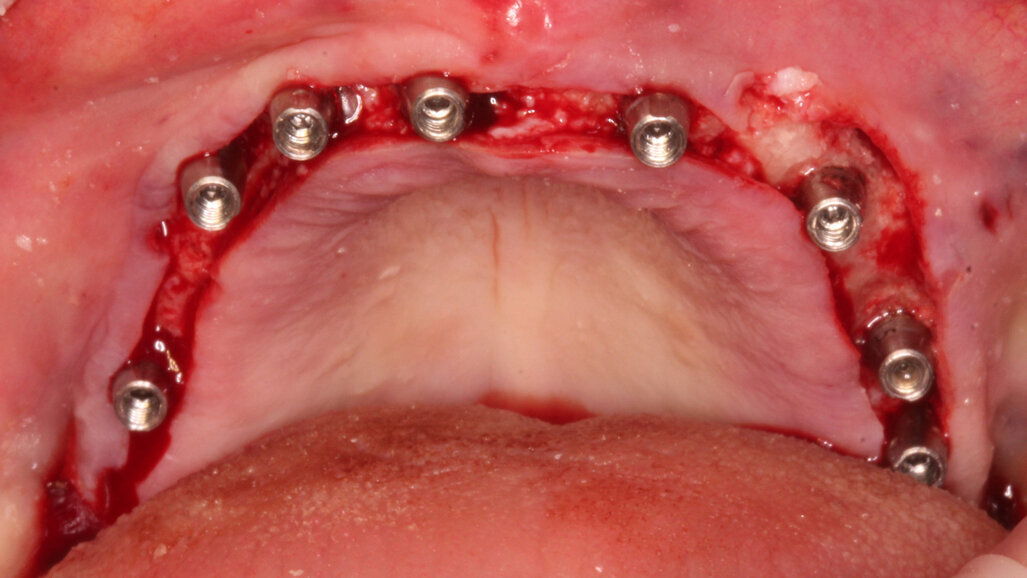

Gli impianti vengono distribuiti lungo tutta l’arcata cercando il parallelismo e limitando il più possibile i cantilever (6-7 impianti superiori e 5-6 impianti inferiori). La scelta di utilizzare i monconi dritti (grazie al parallelismo degli impianti) è da preferire in quanto quest’ultimi sono anche i più robusti e resistenti nel tempo al carico assiale; inoltre caricano l’impianto lungo il suo asse limitando i carichi disassati. Una volta elevato il lembo mucoperiosteo ed evidenziato l’osso alveolare o basale, attenzione deve essere fatta nel fare un’ostectomia riduttiva mediante una fresa a palla del diametro di 0,6-0,8 cm per creare un piano più uniforme possibile tale da formare una piattaforma d’osso alla stessa altezza, guadagnando anche spessore V-L ed uniformità. Gli impianti devono essere posizionati alla stessa altezza tra di loro e distanziati in maniera tale da favorire le manovre di igiene orale inter-implantare. Una volta posizionate le fixture sottocrestali (1-3 mm) come descritto, vanno connessi i monconi solitamente con collare mucoso di 3-4,5 mm in altezza, ponendo particolare attenzione che i tessuti molli suturati non coprano la parte di accoppiamento conometrico. Verificato il parallelismo corretto dei monconi mediante i pin parallelizzatori, siamo certi che l’accoppiamento e la disconnessione delle cappette contenute nella protesi potrà avvenire nel miglior modo possibile senza creare tensioni.

Un’impronta in silicone o digitale sulle cappette in situ accoppiate va presa alla fine della chirurgia, una volta suturati i lembi. Il paziente lascia lo studio con delle cappette provvisorie in Peek a protezione dei monconi e con la sua protesi riadattata oppure con una stampata del Brega riempita con impacco parodontale come medicamento.